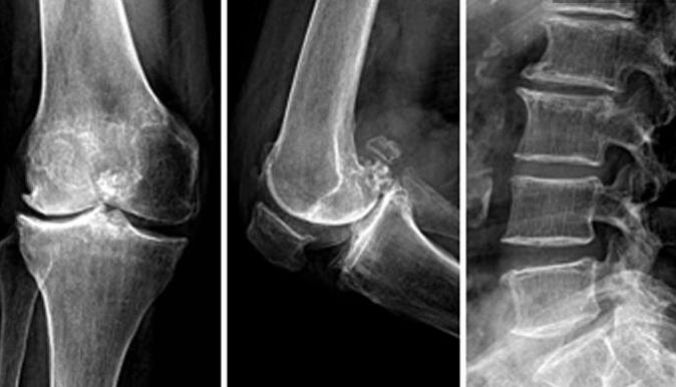

骨关节炎(OA)是发生在滑液关节的一种发展缓慢,以软骨破坏为特征的骨关节疾病,因机械性、代谢、炎症、免疫等因素作用造成,伴有相邻软骨下骨板骨质增生或骨唇形成,可伴有不同程度的滑膜炎症反应,好发于人体负重部位,如膝、髋关节、腰椎等,尤其是膝关节。

1、影像学检查

根据受累关节病情轻重程度,X线片出现的改变可进行一下分级(Kellgren分级):

0级:正常;

1级:可疑有关节间隙狭窄,似有骨赘;

2级:有骨赘,关节间隙可疑狭窄或无;

3级:有中等骨赘形成、关节间隙狭窄、关节面硬化以及关节似有变形;

4级:有大量骨赘形成、明显关节间隙狭窄、关节面严重硬化以及关节变形。